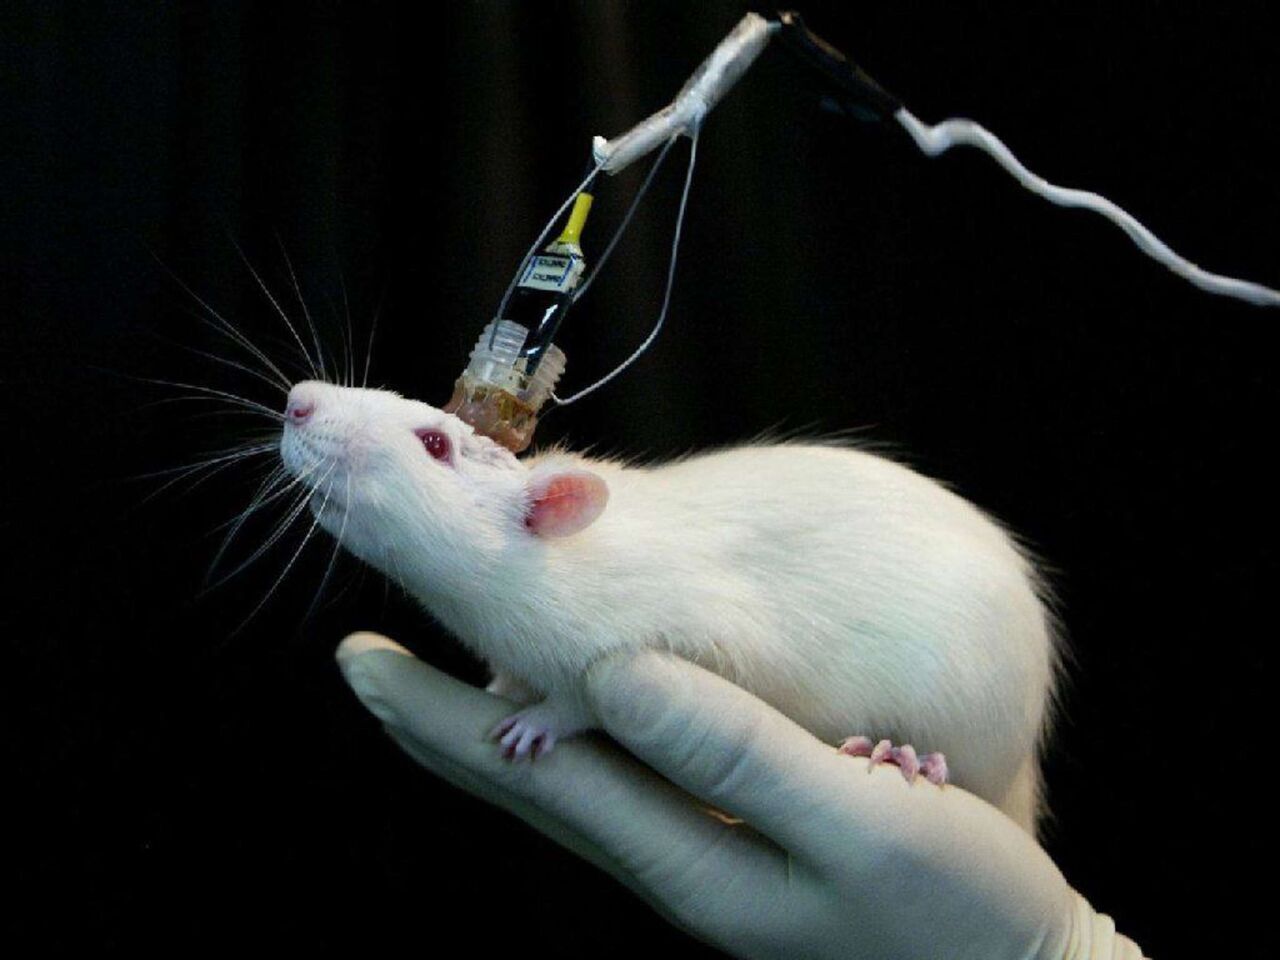

محققان در اسپانیا نانورباتی ساختند که قابلیت کاهش ابعاد تومور را دارد. این ربات خودران، تنها با یک بار تزریق ابعاد تومور را در موشهای مبتلا به سرطان مثانه ۹۰ درصد کوچک کرد.

براساس گزارش تارنمای فیز، به تازگی مقالهای در نشریه نیچر نانوتکنولوژی (Nature Nanotechnology) چاپ شده است که در آن محققان با موفقیت ۹۰ درصدی اندازه تومور سرطان مثانه را در موشها تنها با یک دز استفاده از نانوربات کاهش دادند.

ساموئل سانچز از محققان این پروژه توضیح داد: با یک دز واحد، ما کاهش ۹۰ درصدی در حجم تومور را مشاهده کردیم. چنین رویکرد درمانی کارایی را افزایش میدهد و طول مدت بستری شدن و هزینههای درمان را کم می کند.